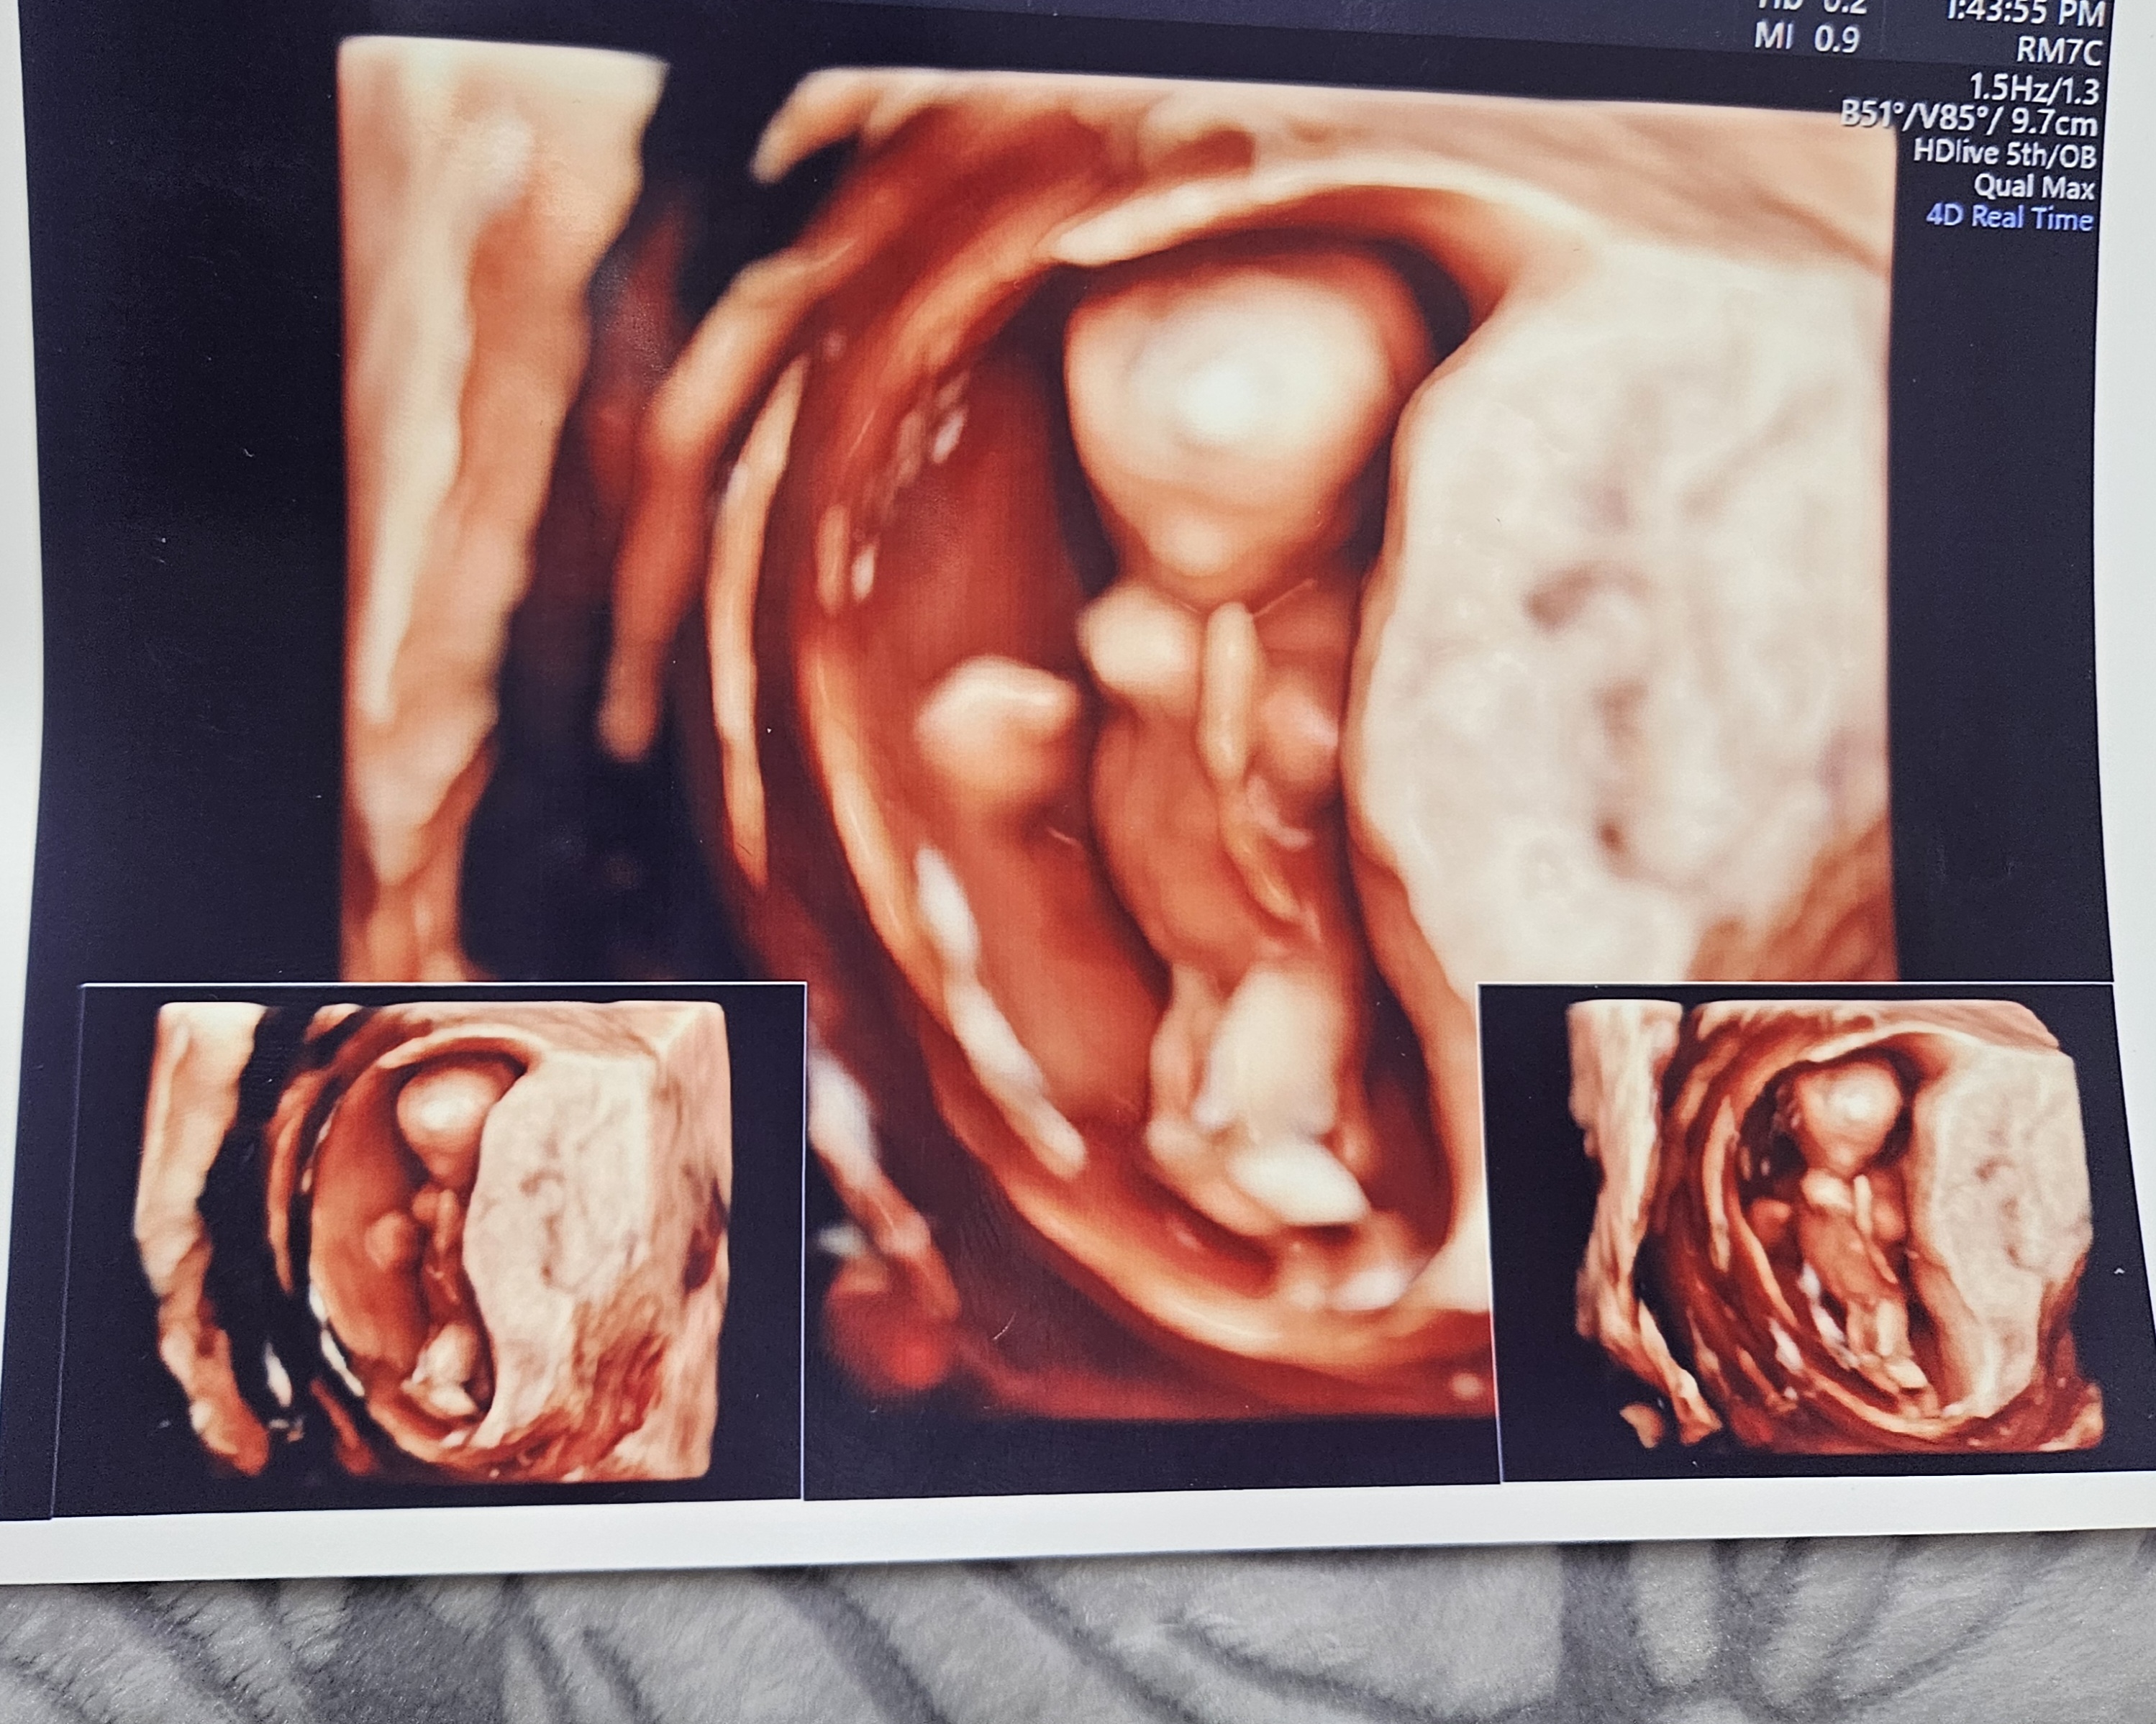

12주때 정밀초음파로는 이 각도로는 구분하기 힘든거 같아요

12주차 3일 되었고 각도법 봐줘요~

12주차 3일 되었고 초음파 사진상으로는 잘 안보일 것 같은데 그래도 혹시 모르니 각도법 한번 봐주세용~! 딸? 아들?